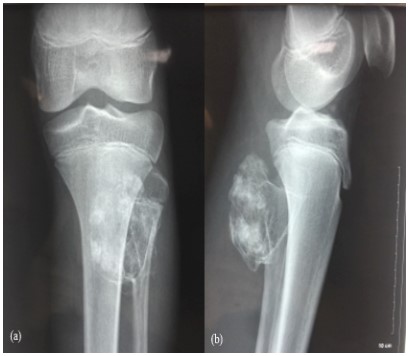

Knee x-ray showed a pedenculated tumor developing from the fibula neck (Figure 1a, 1b) increased in size compared with previous radiographs (Figure 2a, 2b). CT confirm findings with this “cauliflower like” exestosis developing from fibula neck with cartilage cap and with no invasion of the cortical bone (Figure 3).

Figure 1: (a,b) Knee x-ray showing fibular neck pedencu-Knee x-ray showing fibular neck pedenculated tumor with high-density and clear boundaries.

Figure 2: (a,b) increasing in osteochodroma size extending postero-medially.